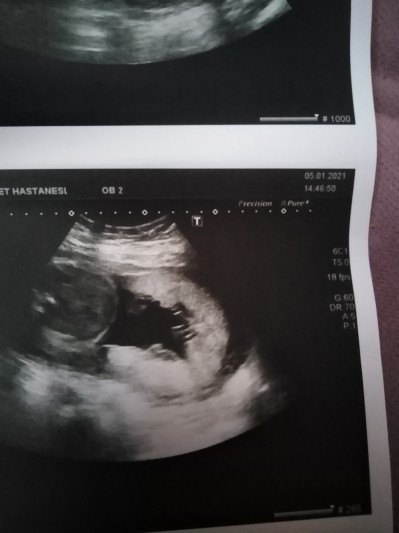

24 haftaligim kızlar sizce cinsiyeti nedir. Doktor ilk kıza benziyor dedi sonra yine kız gibi görünüyor dedi bugün de ne yaptıysak kendini göstermedi şimdi ultrason kağıdına baktım sanki çıkıntı var acaba kordon mudur

Çıkıntı senin fark edemeyeceğin kadar küçük oluyor canım bence kız

Anladım. Bukadar geç gösterdiğine göre kız olabilir sizinkide

Kız olabilir göstermedısw

Bacak arası sanki bu foto degil mi

Valla ben çıkıntı çok net gördüm ama doktor daha iyi bilir